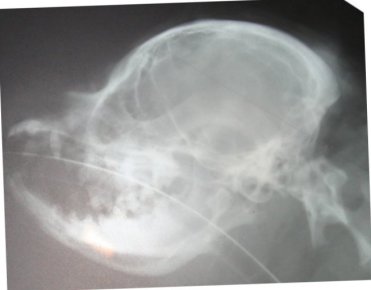

Based on my findings, a study was eventually done to determine

if a skull x-ray could be used to determine amount of CM. The

more CM, the more likely there is to be SM--in most cases. This

study did show there was one skull measurement that did indicate

amount of CM. Here is a comparison of two skull x-rays which

show why this particular measurement indicates amount of CM. The

top one is a skull x-ray of a Cavalier with severe CM (and has

SM as well) and the bottom one is a skull x-ray of a Cavalier

with very little to no CM (and no SM).

The line was drawn from right in front of the 'hole'

(black spot), center of that curved bone (the 'jaw hinge' area)

to where the most thickened area of the skull ends (and the

occipital area begins). In the dog with almost no CM and no SM

you can CLEARLY see there is a lot more lower backskull left

behind/below that line as compared to the dog above--which

literally has almost none! This also happens to be the area

where the cerebellum sits so it would be common sense that the

dog in the top x-ray would have much less room for the

cerebellum than the dog on the bottom--and therefore more CM (chiari

malformation). There just isn't any skull left for there to be

enough room for the cerebellum. It appears here that a good

skull x-ray may be very useful in determining amount of CM and

therefore breeding towards a goal of less and less CM in future

offspring and thereby lessening the prevalence of SM. A skull

x-ray is much cheaper than an MRI which will enable many more

breeders to x-ray for amount of CM in the future as more

information becomes available.